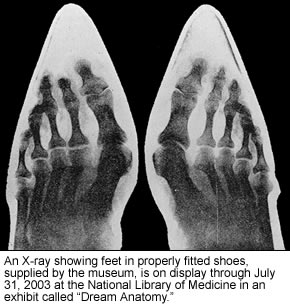

6. Doctors often use X-Rays to examine internal parts of the body to assist their diagnosis. Bone, in particular, shows up very well on film. Try you hand at reading X-Rays by examine the images of X-Rays below and try to ID as many bones as possible. Print out the images and paste them into your NoteBook, labeling them as you go.